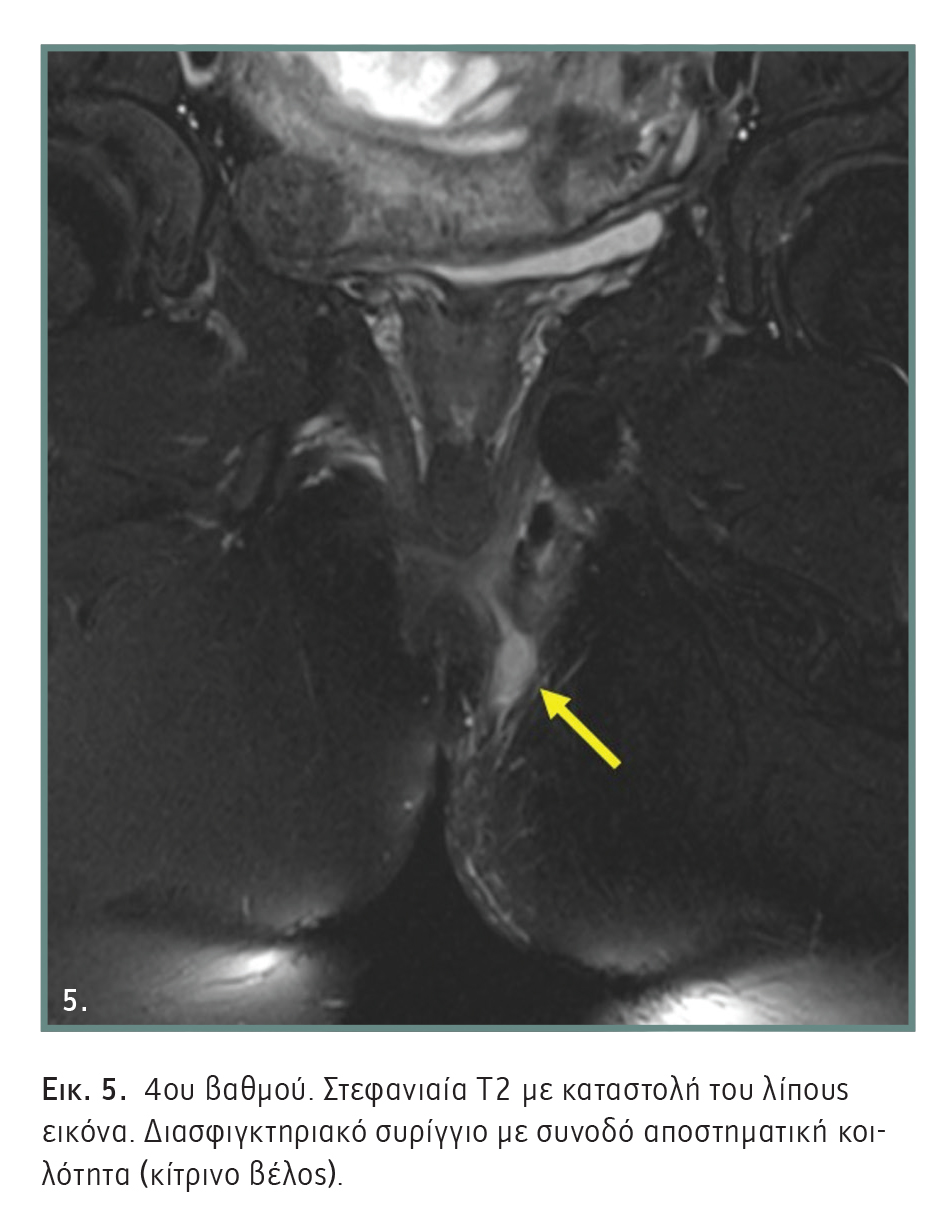

- 4ου βαθμού: Διασφιγκτηριακό συρίγγιο με απόστημα ή δευτερογενή πόρο μέσω του ευθυϊσχιακού και ισχιοπρωκτικού βόθρου. Τα συρίγγια αυτά είναι παρόμοια με εκείνα του 3ου βαθμού, αλλά επιπλέκονται από απόστημα ή δευτερογενή πόρο (Εικόνα 5).